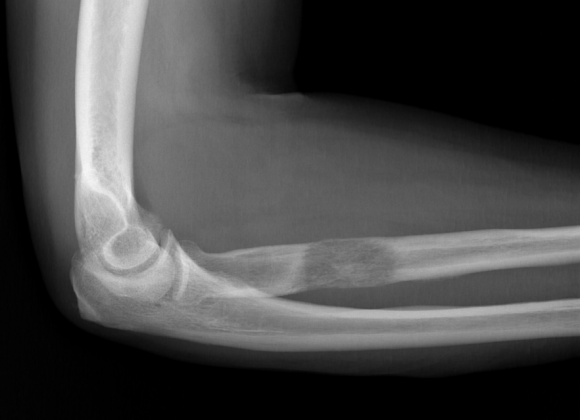

In further tests, the following could be observed: Forearm RX: moth-eaten lytic lesion, poorly defined with cortical destruction of the proximal third with no evidence of associated fracture, compatible with bone metastasis. (Figure 1). Subsequently, the study is extended with an MRI (Figure 2) showing a lytic lesion with cortical invasion and soft-tissue mass in the proximal radius compatible with bone metastasis, invading the supine muscle and probably the extensor digitorum muscle as well as the distal insertion of the biceps tendon. With these findings, the medical oncology service requests a PET CT scan (figure 3) which shows the lesion in the right proximal radius and a partial improvement of the known pulmonary masses alongside a complete response of the bilateral hilar and mediastinal adenopathies. After surgery, a nerve paresis was observed of the radial nerve, which the patient has partially recovered with the help of rehabilitation. Clinically, the patient is no pain and has a mobility limitation of approximately 20º for supination and 10º for the extension.

Radiologically, we find lesions that are typically lytic, with a varying pattern of bone destruction but typically geographic with cortical affectation, without periosteal reaction in most cases, and occasionally with an associated element of soft-tissue mass. In fact, given its clinical and radiological characteristics, they can imitate those of an infection or other non-neoplastic processes such as inflammatory or rheumatoid arthritis 4 , producing a delay in obtaining a definite diagnosis, mainly in patients without a known primary tumour. As a result, inadequate treatment is likely to take place.